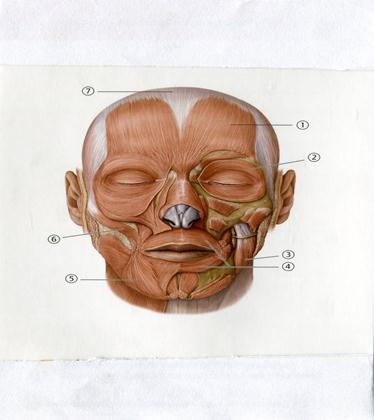

62. Төменде көрсетілген суреттегі белгіленген №2 анатомиялық құрылымды атаңыз.

A. Ауыздың дөңгелек бұлшықеті

B. Бет бұлшықеті

+C. Көздің дөңгелек бұлшықеті

D. Төменгі ерінді түсіретін бұлшықет

E. Ұрт бұлшықеті

63. Төменде көрсетілген суреттегі белгіленген № 7 анатомиялық құрылымды атаңыз.

A. Бет сүйегі

B. Иек тесігі

C. Көзасты тесігі

D. Маңдай сүйек

+E. Мұрын сүйегі